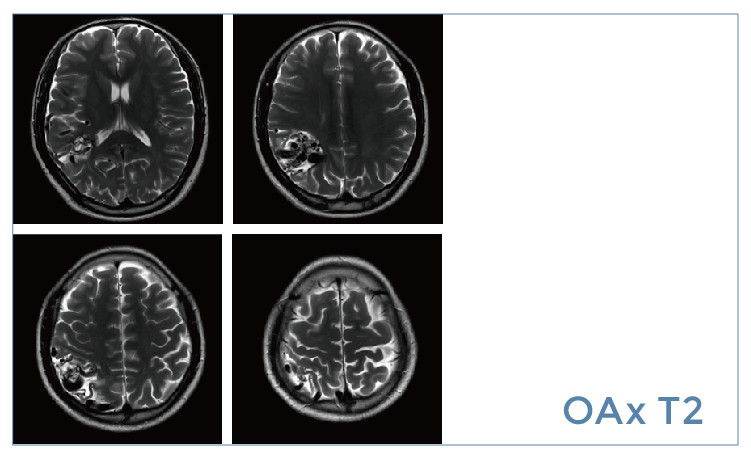

【朗润影像档案】20190531磁共振影像病例结果讨论